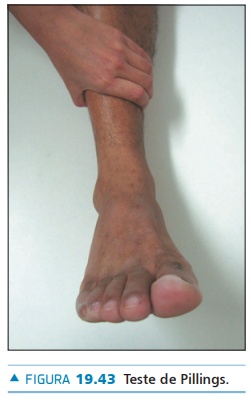

• Exame físico - como é realizado o teste de Pillings (teste da compressão lateral da perna) para avaliação da sindesmose?

A

• Examinador exerce compressão da fíbula contra a tíbia no terço médio da perna

• Pode provocar dor na articulação tibiofibular distal quando houver processo inflamatório local